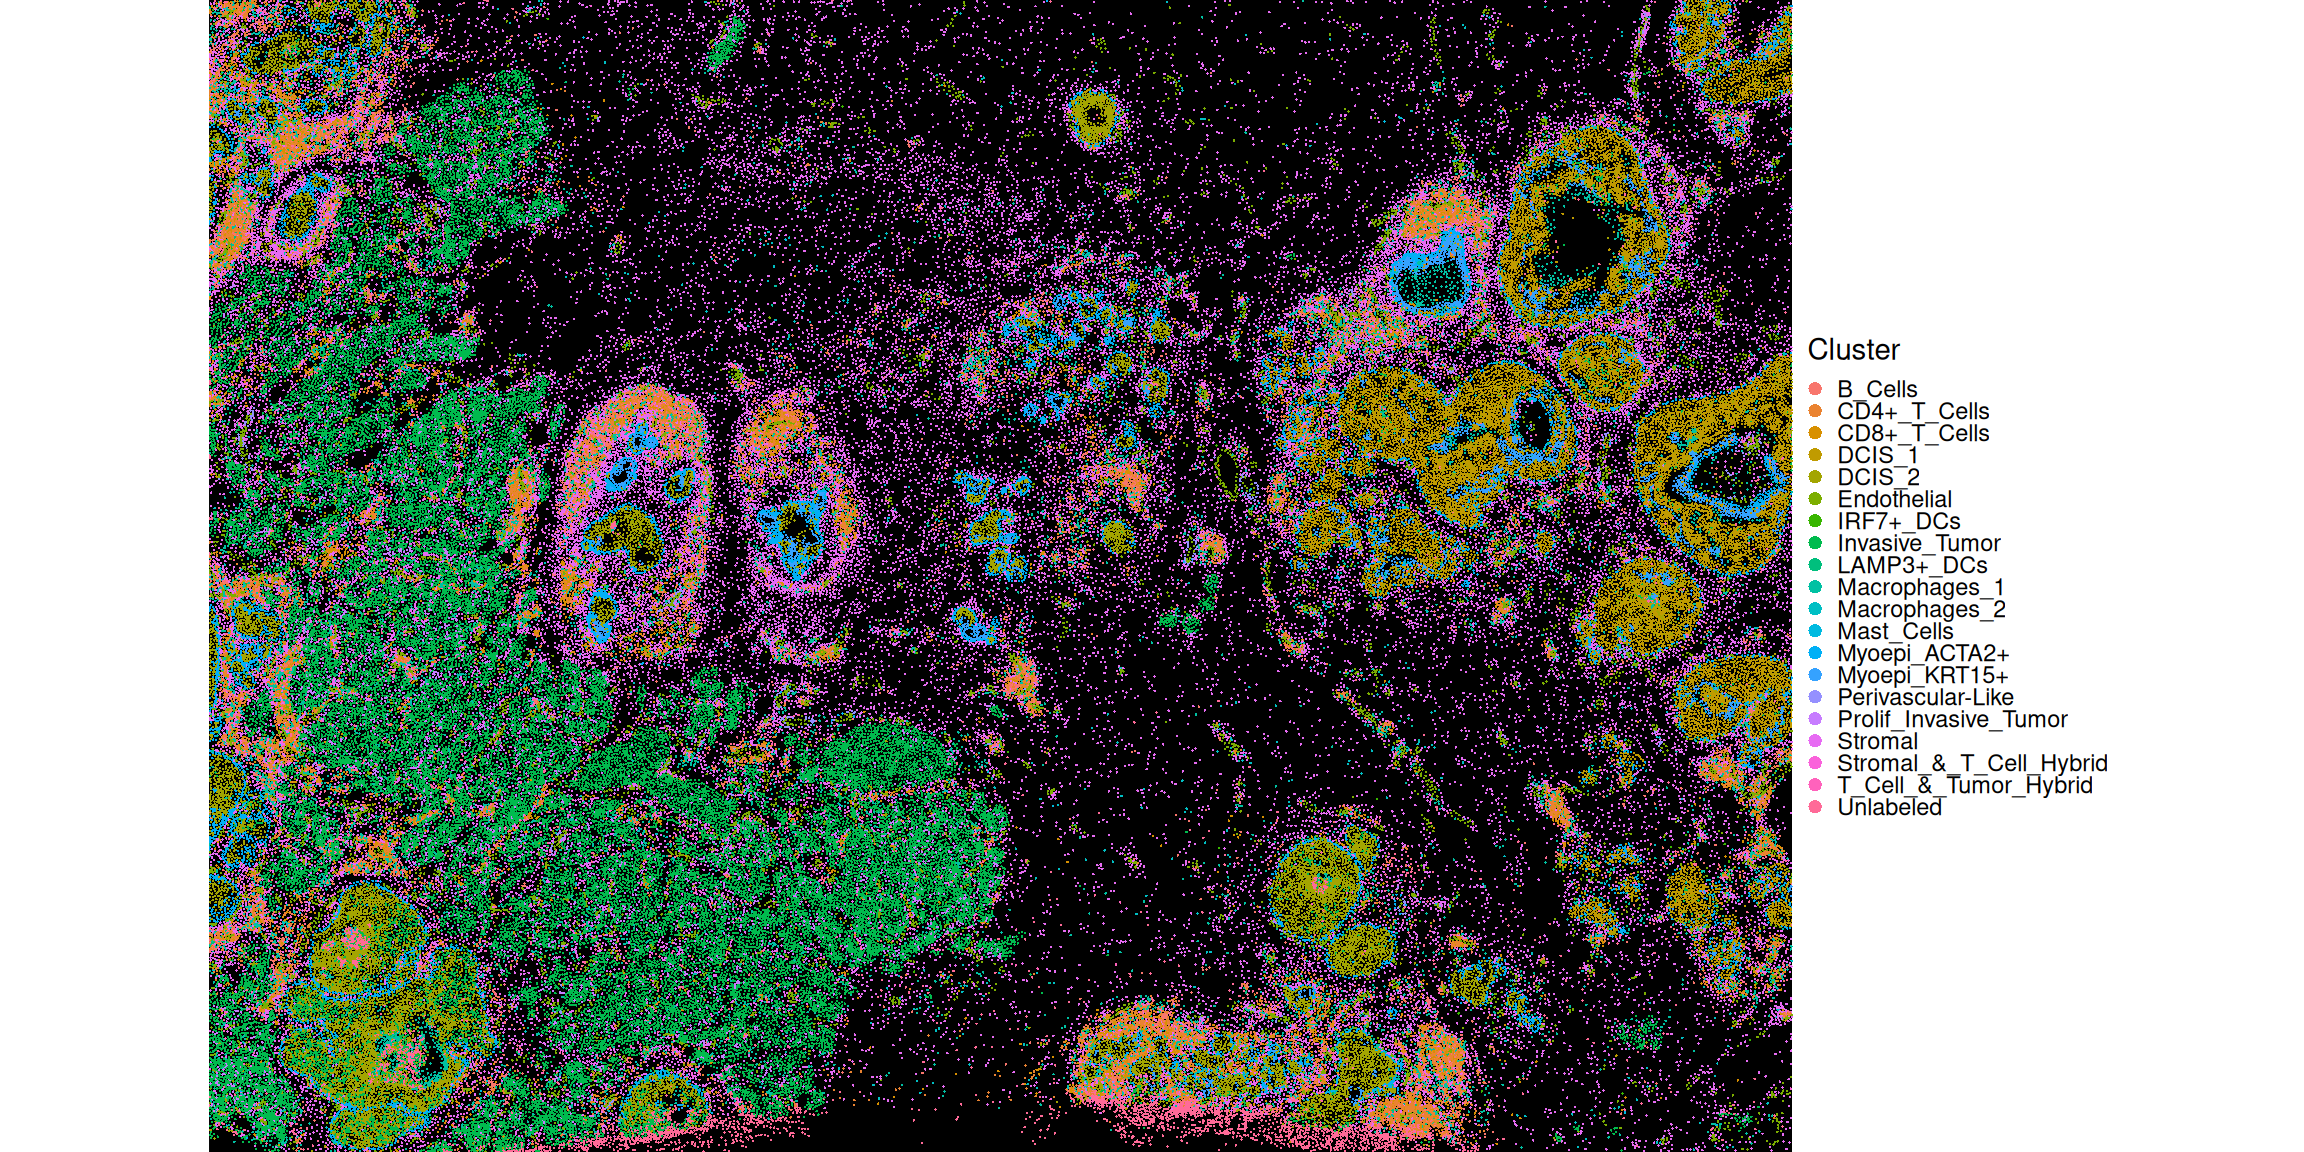

In the plot below, the centroids of the cells are attributed with a discrete cell type mark.

Code

df <- data.frame(xy, colData(sfe))

ggplot(df, aes(x_centroid, y_centroid, col=Cluster)) +

guides(col=guide_legend(override.aes=list(size=2))) +

theme_xy + theme(legend.key.size=ggplot2::unit(0, "pt")) +

geom_point(shape=16, size=0.1)